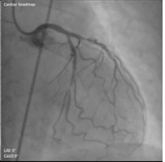

血管撮影

血管撮影とは、足の付け根(鼠径部)や腕の血管から細くて柔らかい管(カテーテル)を体の中に入れ、目的の場所まで進めていき、造影剤という薬を使って血管の形や流れを映し出す検査です。

当院では病気の診断だけでなく、IVR(Interventional Radiology)と呼ばれる治療も積極的におこなっています。IVRとは、画像を見ながら体の中にある病気の部分を治療する方法で、体への負担が少ないのが特徴です。

当院で行っているIVRには、がんや出血、動脈瘤などに対する「塞栓術」という治療、狭くなった血管を広げる「血管拡張術」、脳梗塞や急性下肢動脈閉塞などで詰まった血管の血栓を取り除く「血栓回収術」、胸腹部大動脈瘤に対して「ステントグラフト挿入術」など治療の対象となる部位は、頭から足先までさまざまです。

また、当院には血管撮影専用の装置が3台あり、緊急の治療にもすぐに対応できる体制を整えています。安心して検査・治療を受けていただけるよう、スタッフ一同努めております。